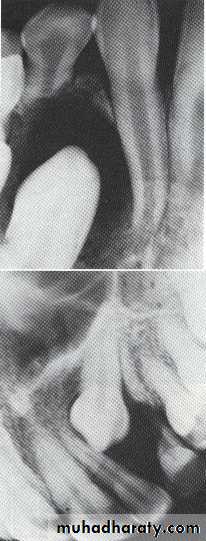

Multilocular appearance, expansion (arrowed) and considerable displacement of the adjacent teeth.

Buccal and lingual expansion (arrowed) and the undulating cortical border.

•Large multilocular aneurysmal bone cyst

in the ramus with marked expansion and

the displacement of/8.